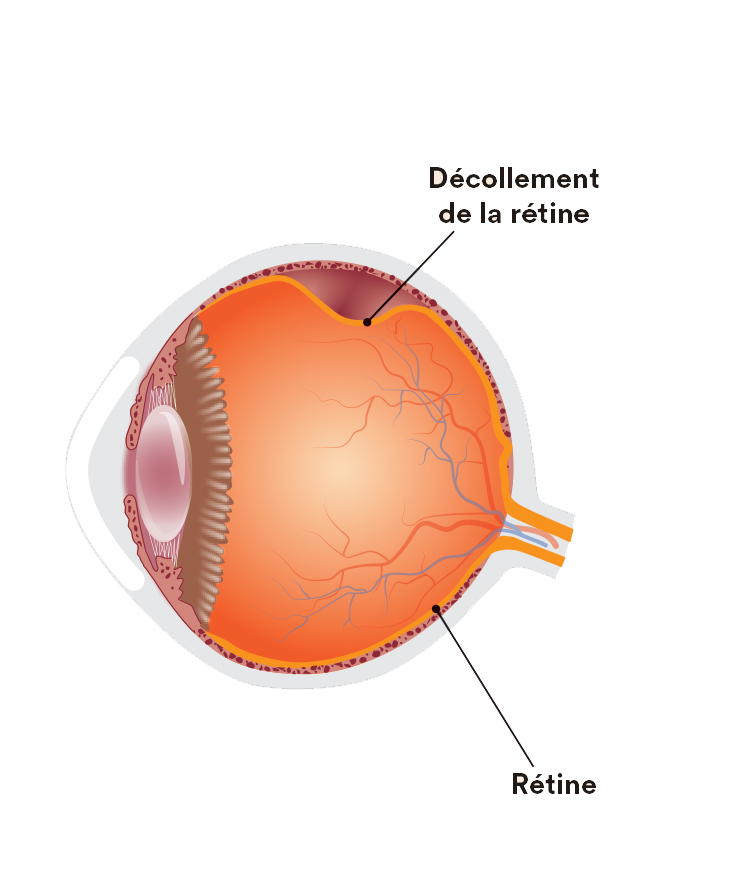

www.ophtalliance.frDécollement De La Rétine - Hôpital Ophtalmique Jules-Gonin

www.ophtalliance.frDécollement De La Rétine - Hôpital Ophtalmique Jules-Gonin

www.ophtalmique.chDécollement De Rétine | Institut De La Rétine | CHU De Nantes

www.ophtalmique.chDécollement De Rétine | Institut De La Rétine | CHU De Nantes